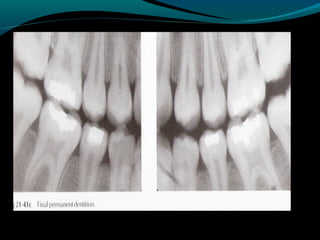

b) Dental age of the patient-

the chronologic age of

the patient is not so important as the

developmental age.Gron studied the

emergence of permanent teeth based on the

amount of root development,as viewed on

radiographs,at the time of emergence.she

found that teeth erupt when three-fourths

of the root is developed,regardless of the

child’s chronologic age.